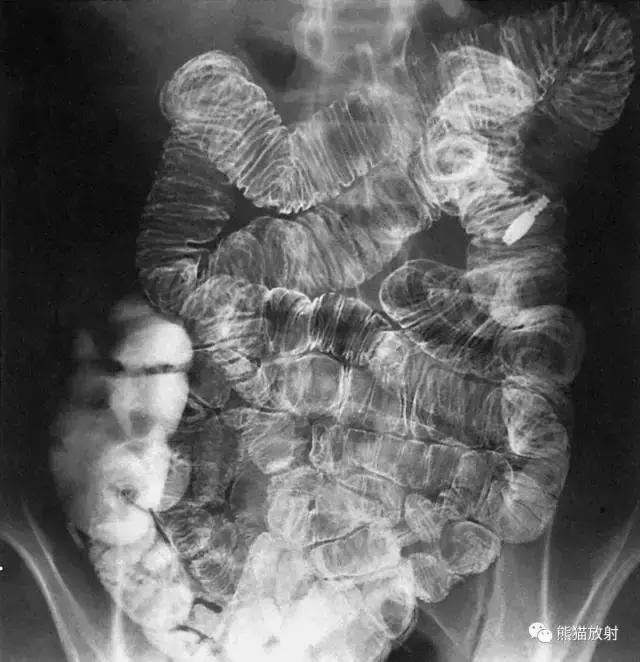

十、结肠

图19 结肠造影

图20 1 结肠脾曲,2 结肠肝曲,3 升结肠,4 横结肠,5 降结肠,6 结肠袋,7 回盲瓣,8 盲肠,9 乙状结肠,10 阑尾,11 直肠